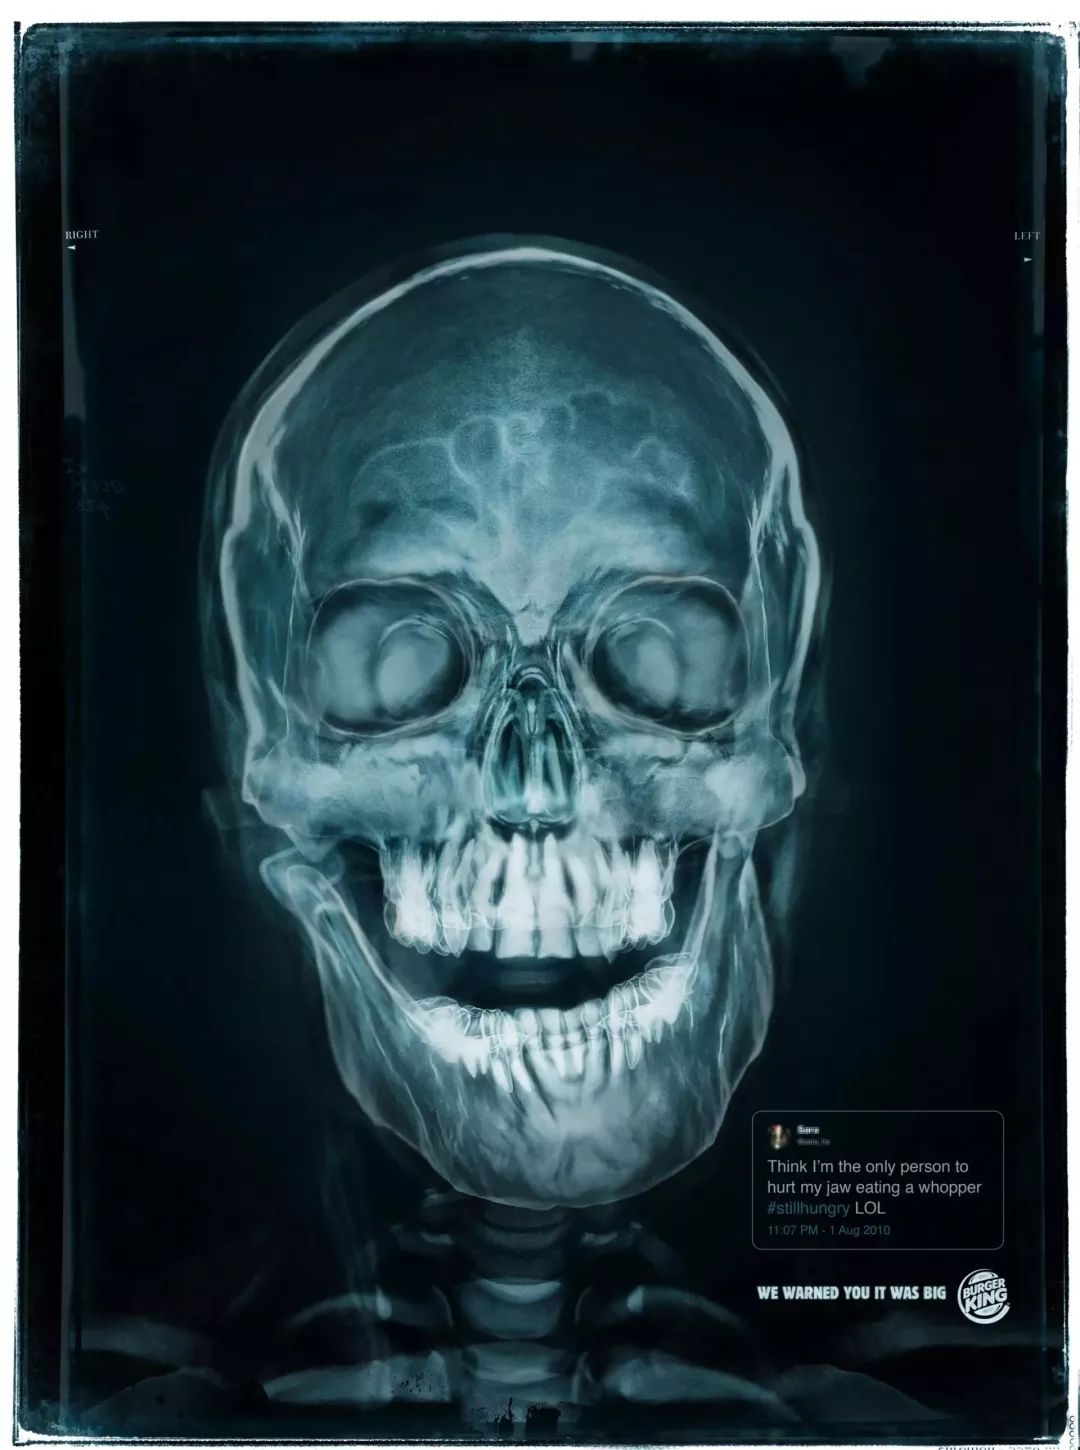

8

<< 滑动查看下一张图片 >>

推完麦当劳,当然不能少了它的对头汉堡王的戏份。汉堡王一直在强调自家的汉堡大,这不,连顾客因为吃自家汉堡导致下巴脱臼的X光都放上来了。把X光片当广告的海报烧脑君还是头回见,结合海报上的温馨提示——“We warned you it was big”,真是让人对汉堡王哭笑不得。